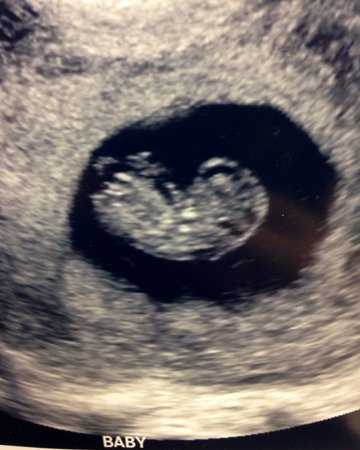

I just got off the phone with my doctor, those nightmare phone calls that leave you feeling more lost and alone then before. He told me all of my quad screening came back good but one. I tested positive for spina bifida. My numbers were 4.01 thats a 1:26. He has ordered me a follow up ultrasound. Has anyone experienced this? & came out just fine? I know my numbers are drastically high, I attached a pic of my 9wk maybe someone can see something. Im currently 18 weeks pregant and only 20 years old.